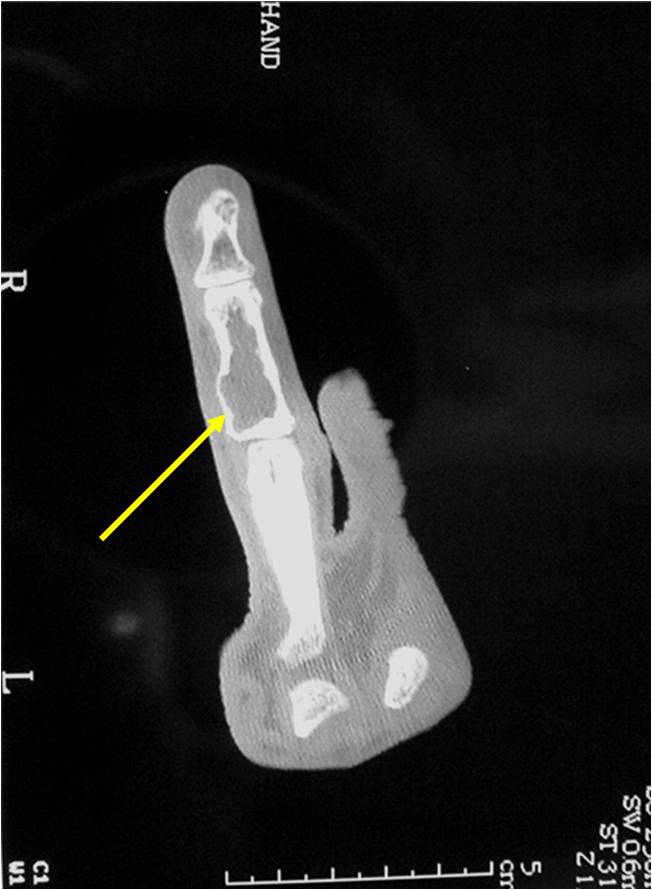

- MRI is better to see noncalcified chondroid lesions and the full extent of lesions

- MRI

- Lobulated margin

- Marked increased intensity long TR images

- Calcified chondroid – low intensity all sequences

MRI:

- Lobulated margin (Lobular Growth Pattern)

- T1 Weighted Images: Intermediate Signal Intensity

- Calcifications will be low signal

- T2 Weighted Images: High Signal Intensity

- High water content shows as high signal on T2 weighted images

- There should never be any cortical destruction nor a soft tissue component. If this exists then the tumor must be a chondrosarcoma.

- Endosteal scalloping and cortical expansion is acceptable for phalangeal tumors. In most benign long bone cartilage tumors there is minimal endosteal scalloping but there should be no cortical expansion nor thickening. There should be no cortical destruction and no soft tissue component associated with an enchondroma. Cortical destruction, periosteal thickening, cortical expansion and a soft tissue component indicates a chondrosarcoma of the long bone.